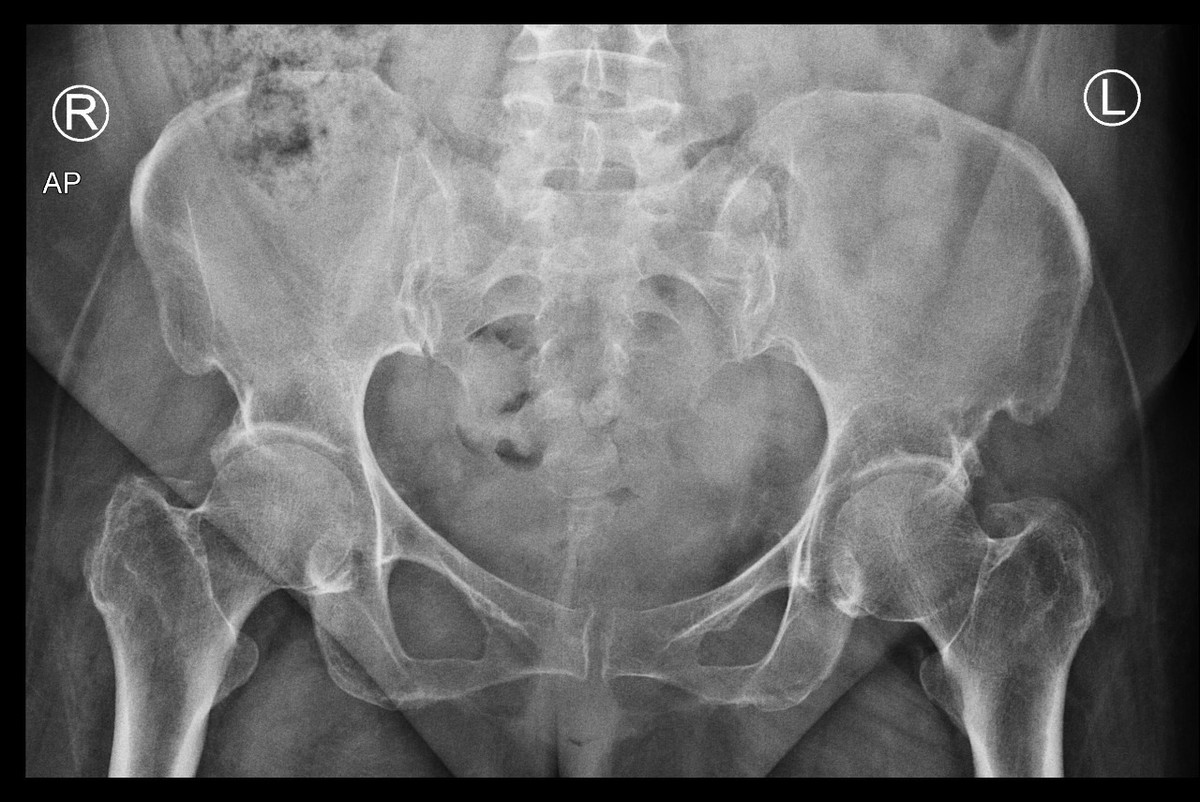

في كل يوم اسمع أمي ومن هم حولي من كبار السن يعانون من الآم مستمرة في العظام تحديدًا في منتصف الظهر والورك الأيمن والأيسر والركبتين، فهذه المناطق أرى أن أكثر كبار السن يشتكون منها. المراجعات الخاصة بالمسشتفى بلا فائدة، الأدوية كذلك. تأثرت صحة أمي كثيرًا فلم تعد تمارس اعمالها كما في السابق ولم تعد حتى تقدر على طلوع الدرج ولا الجلوس كثيرًا. وهذه بعض صور الخاصة بأشعة العظام عندما تم فحصها